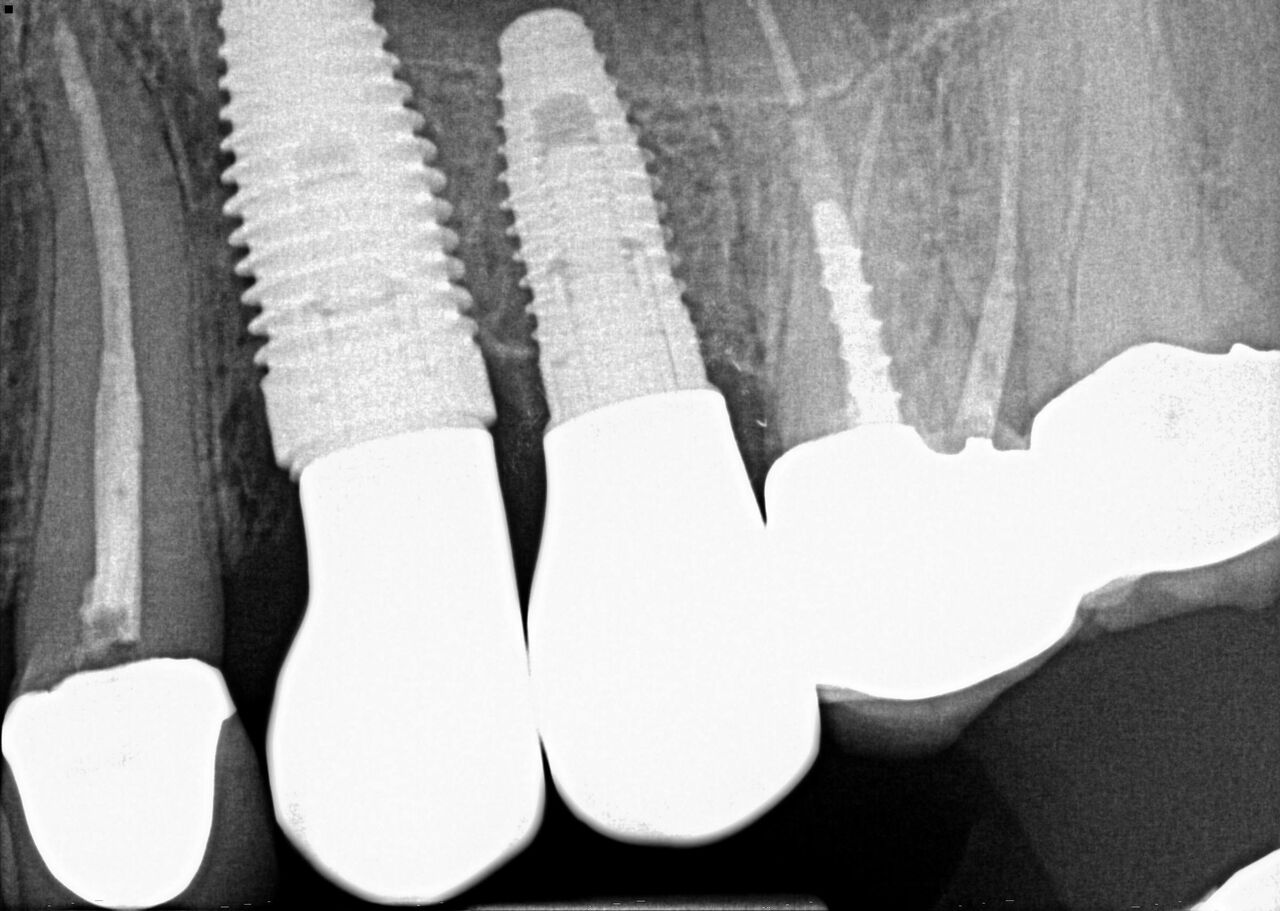

(24.) Radiograph of postoperative individual crowns on Nos. 6 through 10.

Figure 24

(25.) Radiograph of postoperative individual crowns on Nos. 6 through 10.

Figure 25

A 42-year-old man presented with a very loose bridge on Nos. 6 through 9 with periodontally compromised retainers on Nos. 6 and 9 (Figure 17 through Figure 19), and endodontically involved No. 10 with a calcified canal. Teeth Nos. 6, 9, and 10 were extracted, the sockets fully debrided, and pontic soft tissue on Nos. 7 and 8 sculpted to be symmetrical in soft tissue contour with the contralateral lateral incisor and central incisor locations. Implants were secured in position Nos. 6 through 10 (Figure 20) in excess of 45 Ncm, the bone was milled to provide unimpeded seating of temporary abutments, and temporary crowns were fabricated chairside and adjusted to be out of occlusion in centric relation and all excursions. The temporary crowns were cemented after extrusion of excess cement extraorally and the patient was prescribed antibiotics, analgesics, and instructed in postoperative care particular to immediately provisionally restored implants. At 6 months, integration was confirmed (Figure 20 through Figure 23) and after placement of scanning abutments, the implants and soft tissues were scanned. Final crowns were fabricated from the scanned images and were cemented after extrusion of excess cement extraorally (Figure 24 through Figure 26), and oral hygiene procedures were reviewed.